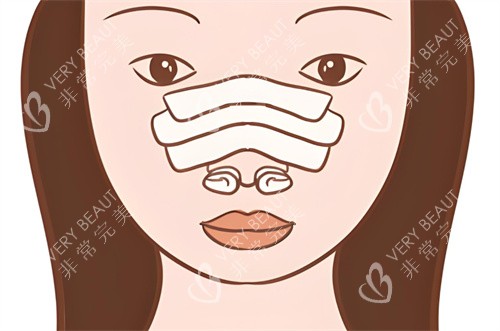

他擅长采用肋软骨、鼻中隔等自体材料进行鼻部重建,重视鼻部功能与形态协调。尤其在处理鼻小柱疤痕、鼻翼后缩、鼻孔不对称等复杂问题时经验充足。

李医生强调鼻部设计的整体协调,推崇自然风格的鼻型。术后结果不仅触感柔软,还可揉捏,且长期稳定性较好,力求减少再次修复的可能。

从公开病例来看,李保锴医生曾处理过多例高难度修复手术,包括四次鼻修复史及注射物取出的情况。术后结果在形态和对称度上均有良好表现,受到较多患者认可。

手术与术后维持